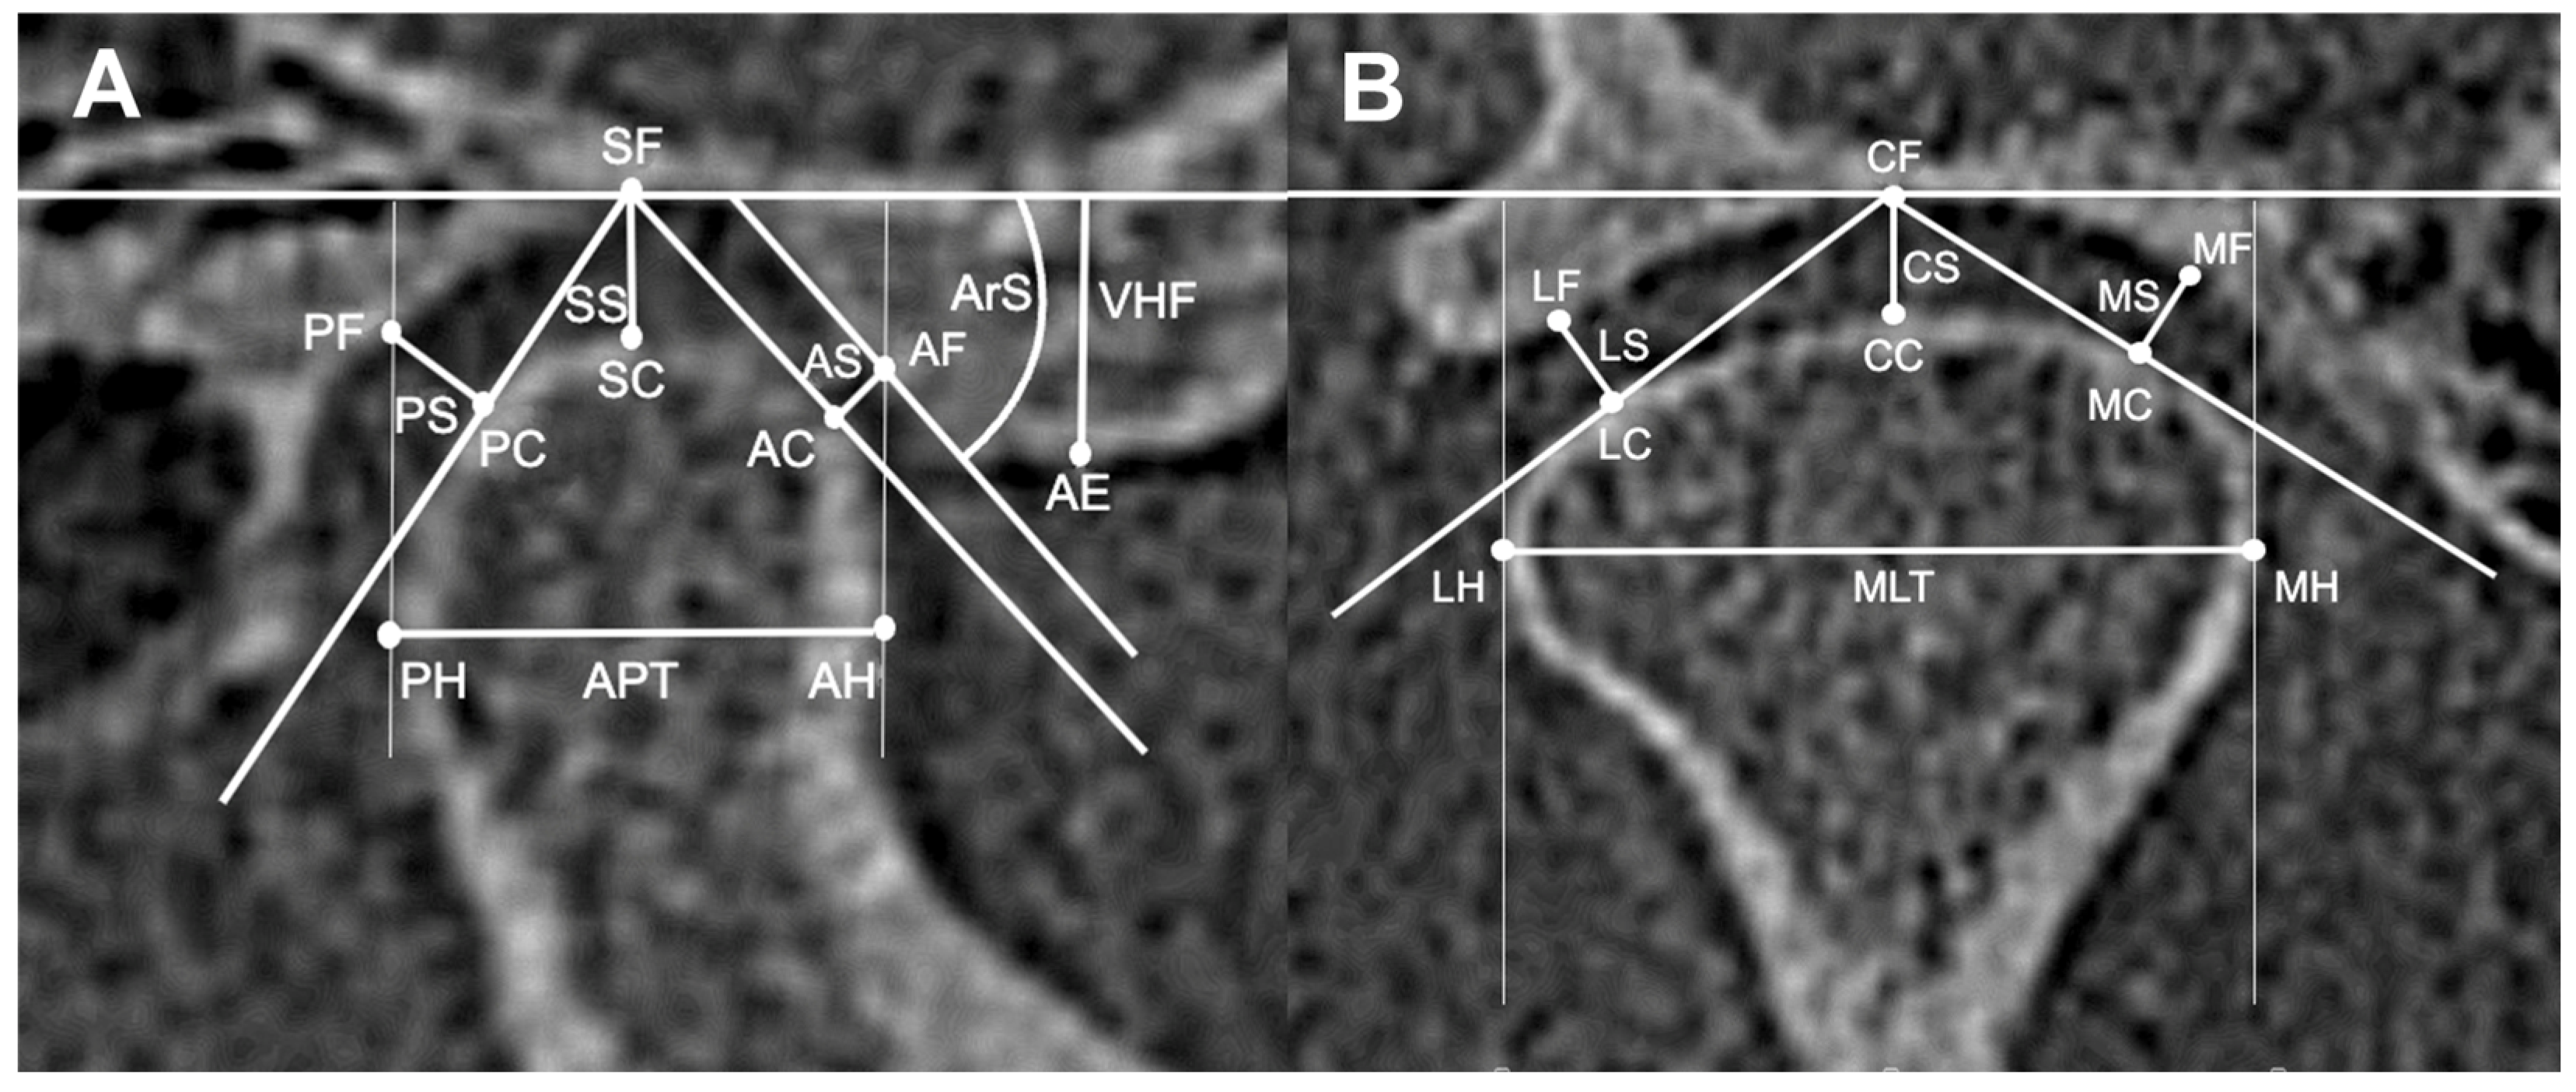

| Sagittal view | AS (mm) | 2.21 A | 1.00 | 0.62 | 2.40 A | 0.67 | 2.05 A | 0.51 | <0.001 (0.002) **/ η2 = 0.02 | ||

| SS (mm) | 3.38 B | 1.61 | 0.88 | 3.69 B | 0.90 | 3.10 B | 0.77 | <0.001 ***/ η2 = 0.03 | |||

| PS (mm) | 2.46 A | 1.18 | 0.71 | 2.59 A | 0.72 | 2.34 A | 0.69 | 0.044 (0.035) */ η2 = 0.008 | |||

| ArS (°) | 50.04 | 17.42 | 8.54 | 51.54 | 8.22 | 48.69 | 8.65 | 0.053/η2 = 0.008 | |||

| VHF (mm) | 7.30 | 2.55 | 1.27 | 7.73 | 1.26 | 6.91 | 1.16 | <0.001 ***/η2 = 0.02 | |||

| APT (mm) | 8.65 | 3.05 | 1.07 | 8.68 | 1.17 | 8.63 | 0.97 | 0.784/η2 = 0.0004 | |||

| Coronal view | MS (mm) | 3.05 A | 1.00 | 0.85 | 3.24 A | 0.84 | 2.88 A | 0.83 | 0.014 (<0.001) ***/ η2 = 0.03 | ||

| CS (mm) | 3.39 B | 1.15 | 0.88 | 3.71 B | 0.92 | 3.11 B | 0.74 | <0.001 (<0.001) ***/ η2 = 0.03 | |||

| LS (mm) | 2.30 C | 0.79 | 0.71 | 2.51 C | 0.84 | 2.12 C | 0.52 | <0.001 (0.009) **/ η2 = 0.01 | |||

| MLT (mm) | 19.27 | 2.32 | 20.56 | 2.11 | 18.10 | 1.85 | <0.001 ***/ η2 = 0.07 | ||||